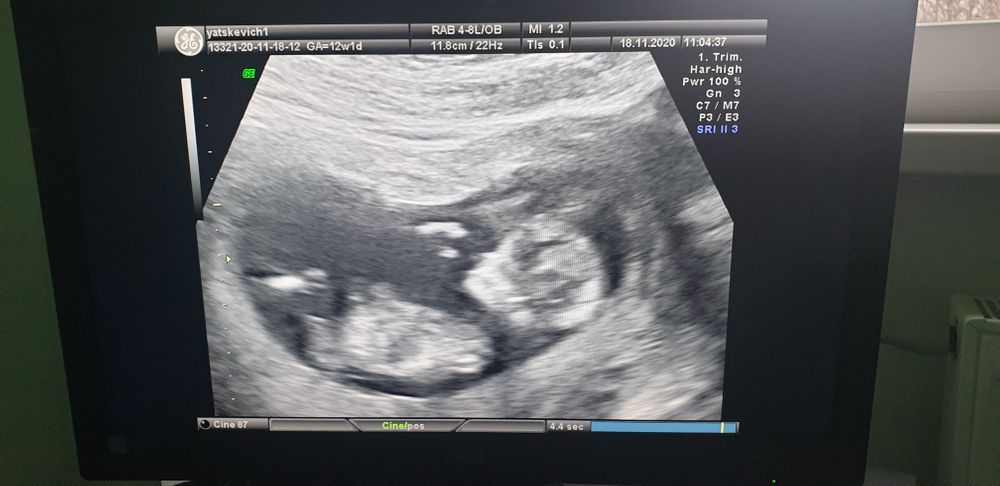

12 недель - полёт нормальный!

Сегодня была на 1ом скрининге. Увидела свою крошку, уже прям человек)

Развиваемся отлично, КТР 56,2 мм, воротниковое пространство 1,6 мм. В заключение написано, что идём точно в срок. 12 +1 как и по М. До сих пор не очень понимаю как на УЗИ смотрят срок, т.к. все таблицы в интернете показывают, что мы отстаём, как по первому УЗИ, так и сейчас.

Ещё поставили предлежание плаценты, и дали наказ беречь себя)